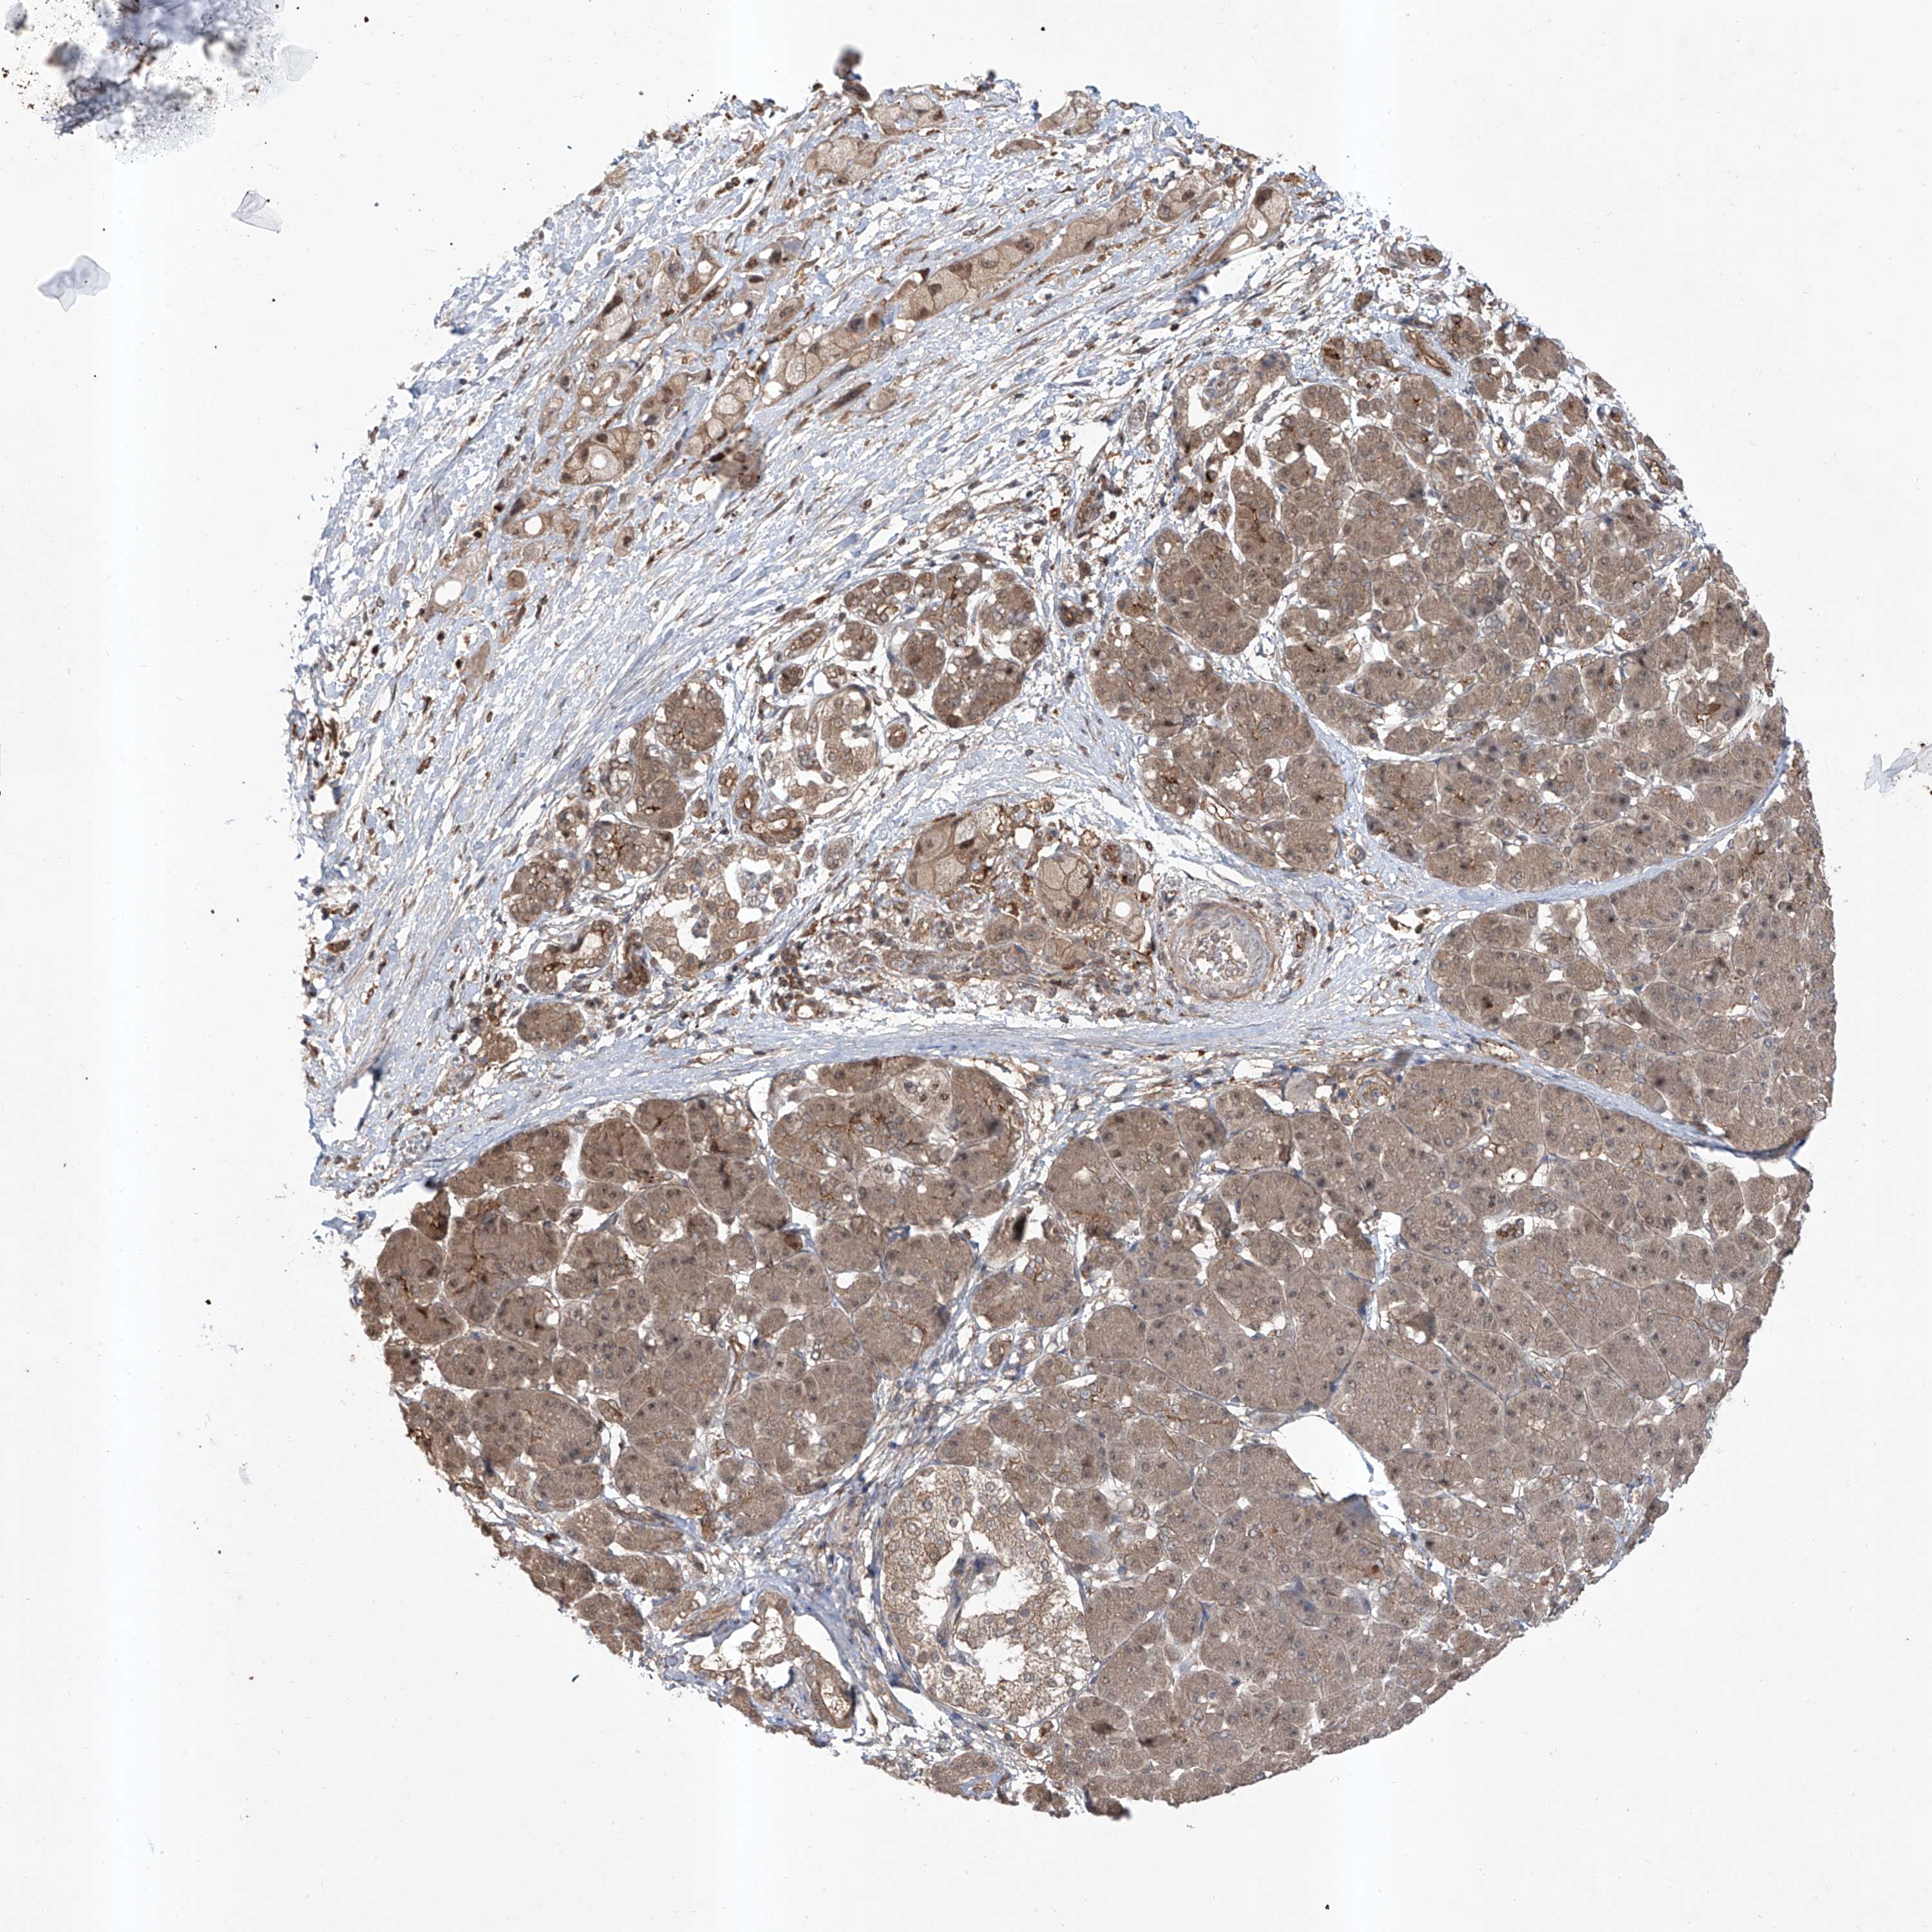

PANCREATIC CANCER - Protein expressioni

A mouse-over function shows sample information and annotation data. Click on an image to view it in a full screen mode. Samples can be filtered based on level of antibody staining by selecting one or several of the following categories: high, medium, low and not detected. The assay and annotation is described here.

Note that samples used for immunohistochemistry by the Human Protein Atlas do not correspond to samples in the TCGA dataset.

Antibody stainingi

Antibody staining in the annotated cell types in the current human tissue is reported as not detected, low, medium, or high, based on conventional immunohistochemistry profiling in selected tissues. This score is based on the combination of the staining intensity and fraction of stained cells.

Each image is clickable and will lead to virtual microscopy that enables deeper exploration of all samples and also displays staining intensity scores, fraction scores and subcellular localization as well as patient and tissue information for each sample.

Antibody HPA028911

Antibody CAB037020

Staining

High

Medium

Low

Not detected

Intensity

Strong

Moderate

Weak

Negative

Quantity

>75%

75%-25%

<25%

None

Location

Nuclear

Cytoplasmic/membranous

Cytoplasmic/membranous,nuclear

Adenocarcinoma, NOS